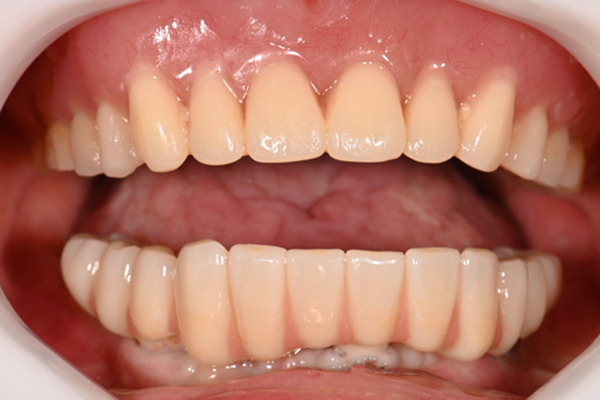

| 主訴 | 全体的にきれいにしたい |

| 治療内容 | 午前中に上下顎共に重度の歯周病、虫歯のため全ての歯を抜歯させていただき下顎はインプラントの土台を3本埋入し歯型を取り午後に上部構造(下顎全ての歯)を装着、上顎は一度総入れ歯を装着させていただきました。 治療が1日で完了しその日のうちに噛めるようになります。 |

| 治療期間 | 2回(1回目に資料取りをさせていただき2回目に下記の全ての治療をさせていただきました。) |

| 治療費 | 250万円 |

| 治療 リスク | 抜歯した部位などに関しては当日痛みが出ますので痛み止めなどを処方させていただきます |